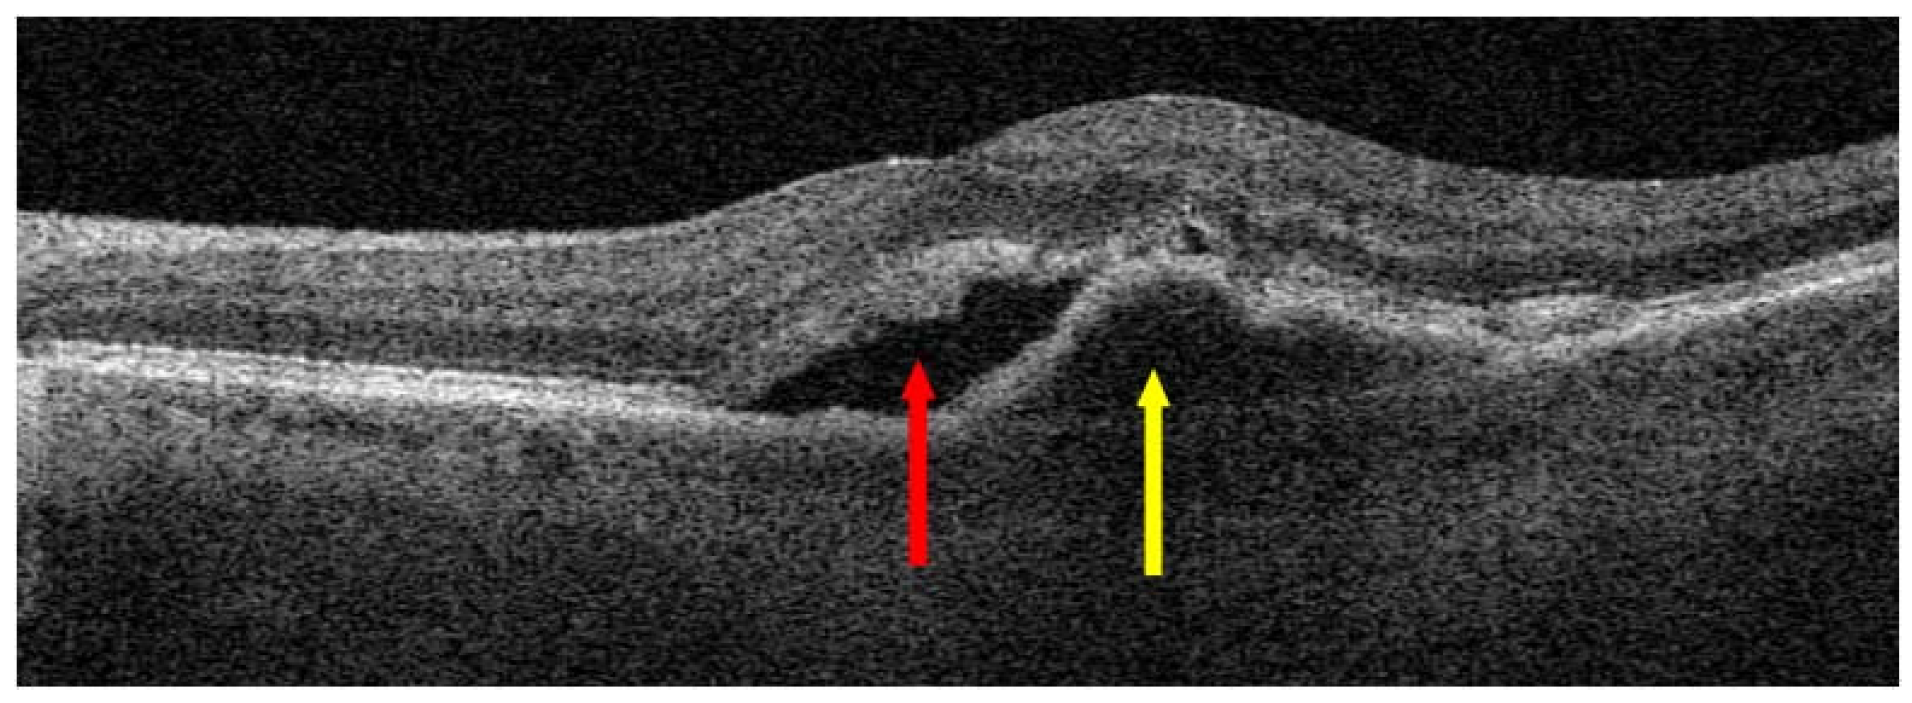

- Spaide, R.F.; Jaffe, G.J.; Sarraf, D.; Freund, K.B.; Sadda, S.R.; Staurenghi, G.; Waheed, N.K.; Chakravarthy, U.; Rosenfeld, P.J.; Holz, F.G.; et al. Consensus Nomenclature for Reporting Neovascular Age-Related Macular Degeneration Data: Consensus on Neovascular Age-Related Macular Degeneration Nomenclature Study Group. Ophthalmology 2020, 127, 616–636. [Google Scholar] [CrossRef]

- Hilely, A.; Au, A.; Freund, K.B.; Loewenstein, A.; Souied, E.H.; Zur, D.; Sacconi, R.; Borrelli, E.; Peiretti, E.; Iovino, C.; et al. Non-neovascular age-related macular degeneration with subretinal fluid. Br. J. Ophthalmol. 2021, 105, 1415–1420. [Google Scholar] [CrossRef]